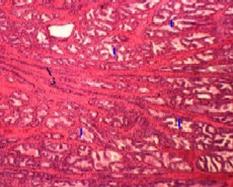

| 3,б-г. Препарат - предстательная железа собаки. Окраска гематоксилин-эозином. | ||

(Малое увеличение) б)Полный размер | (Другое поле зрения) в)Полный размер | (Большое увеличение) г)Полный размер |

| Концевые отделы | 1. По форме концевых отделов (1) ж е лезы простаты являются альвеолярно-трубчатыми. 2. В этих отделах – по крайней мере, три вида клеток: главные клетки – слизистые экзокриноциты кубической или призматической формы, вырабатывающие - все компоненты секрета простаты - и (как полагают некоторые авторы) несколько гормонов (см. выше); базальные, или стволовые, клетки – выглядят как мелкие вставочные клетки; относительно редкие эндокринные клетки, синтезирующие гормоны с паракринным действием. 3. Концевые отделы окружены гладкими миоцитами (2), чьё сокращение облегчает опорожнение концевых отделов при эякуляции. |

| Выводные протоки | 1. Выводные протоки (3), отходящие от концевых отделов, направляются к мочеиспускательному каналу (4). 2. а) У человека они имеют более широкий просвет, чем концевые отделы. б) У собаки же (как видно на снимке) протоки очень узкие. 3. В крупных выводных протоках эпителий - многорядный. |

| Группы желёз | По локализации железы простаты делят на 3 группы: железы в составе слизистой оболочкимочеиспускательного канала; железы в соединительной ткани вокруг мочеиспускательного канала, железы, находящиеся в остальной части простаты (и представляющие собственно предстательные железы). |